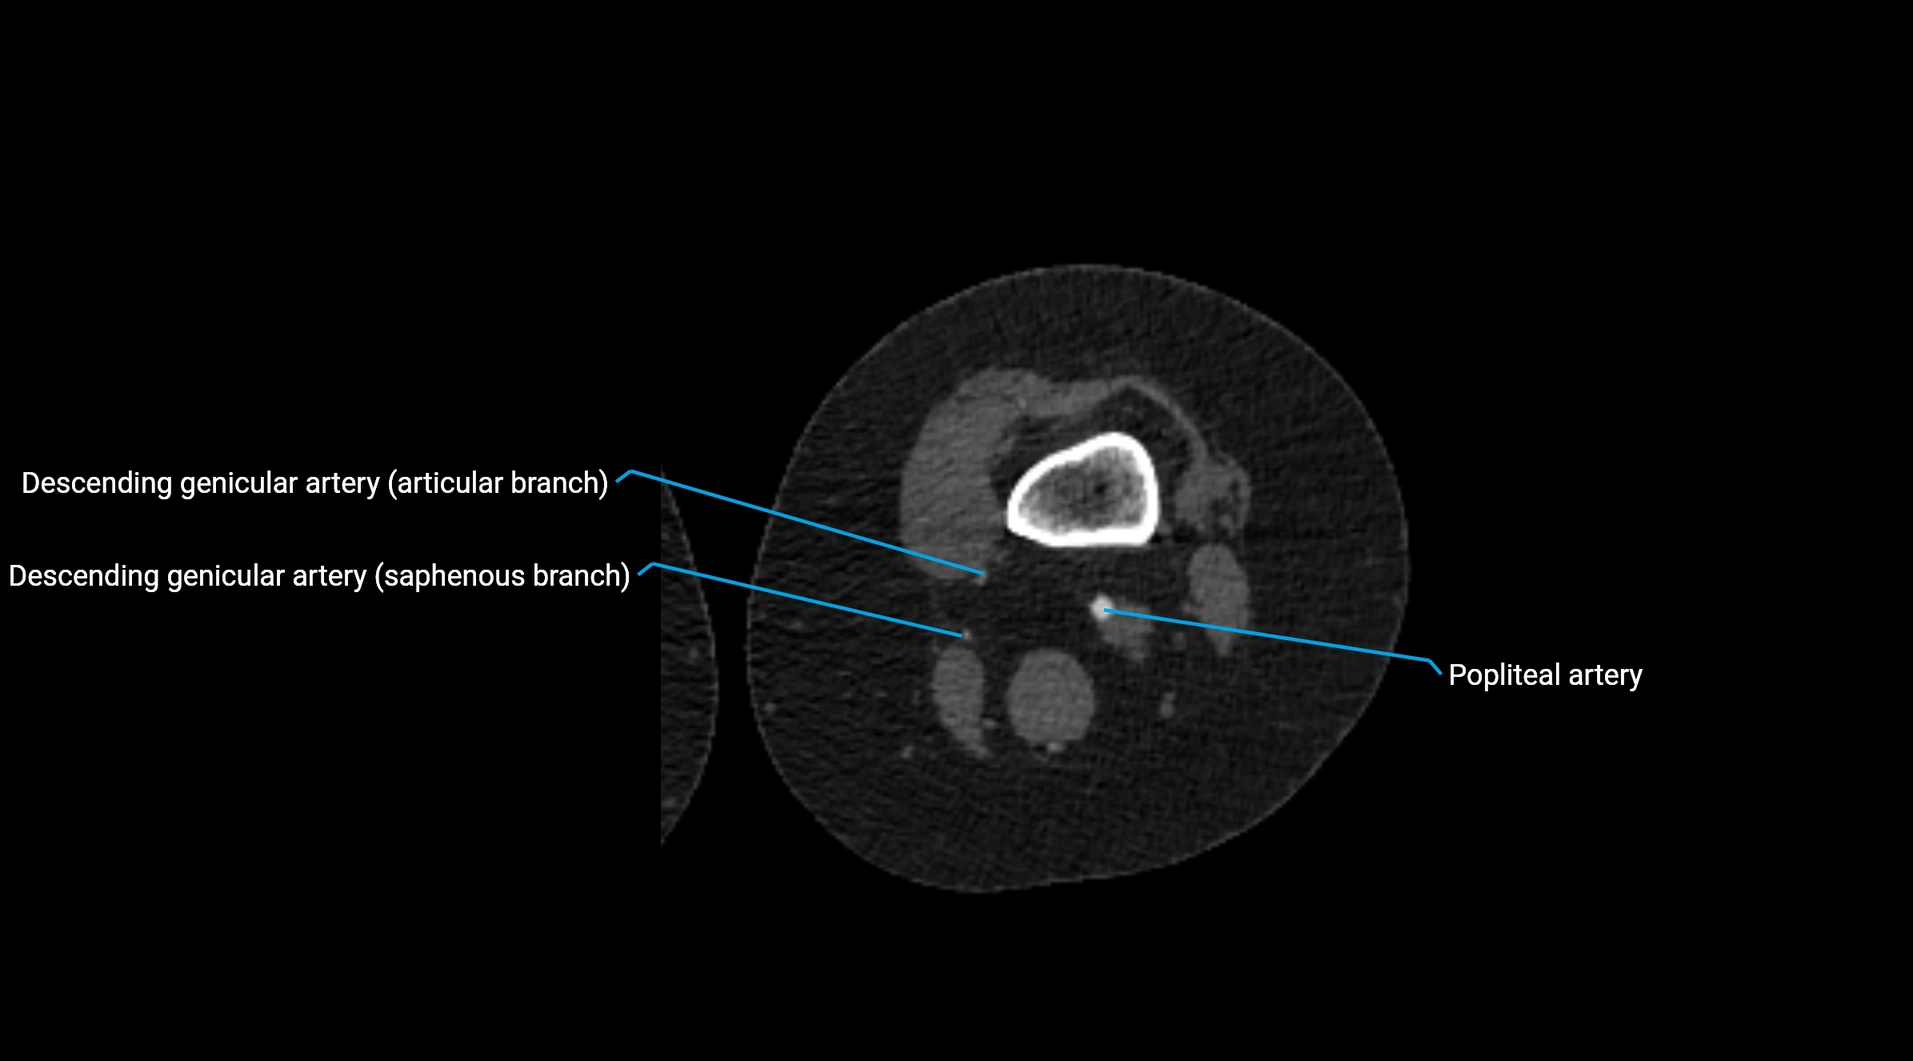

CT images

image